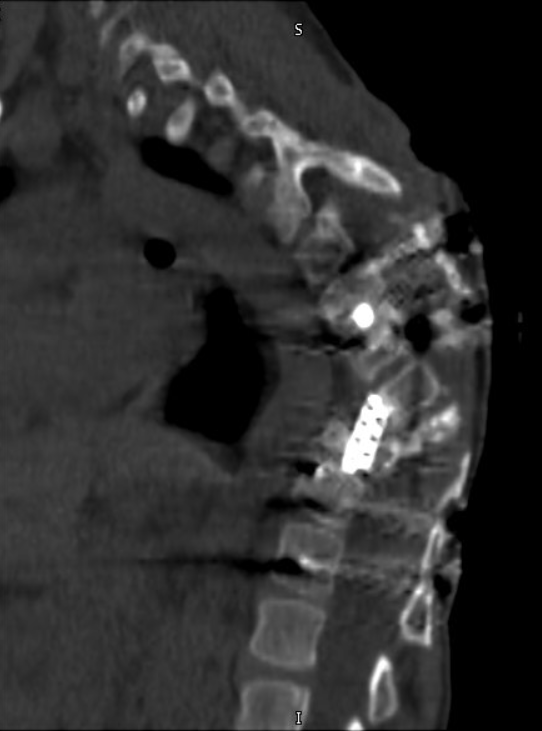

En las valoraciones iniciales, nos mencionaban que su forma de caminar podía deberse a otras causas y que podría mejorar con el uso de plantillas. Sin embargo, como papás, no nos quedamos con esa duda. Buscamos segundas opiniones y realizamos estudios más específicos RM y TAC.

During the initial evaluations, we were told that the way he was walking could be due to other causes and that it might improve with the use of orthopedic insoles. However, as parents, we could not ignore our concerns. We sought second opinions and pursued more detailed studies, including MRI and CT scans.

Today we know that Jorge Luis is facing another serious problem in his spine.

Hoy sabemos que Jorge Luis enfrenta nuevamente un problema en su columna.